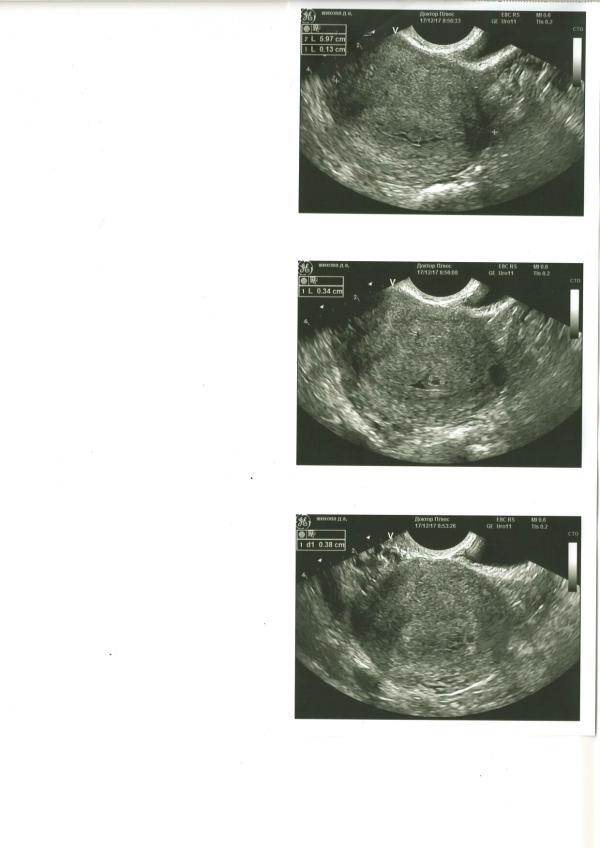

Не выдержала, сходила на УЗИ. Плодное яйцо - 3,6 мм, полость матки расширена до 1,5 мм, анэхогенное содержимое. Полагаю что это содержимое и есть та сама кровь, которая выделялась при походе по "большим делам". Сейчас никаких выделений нет, пью дюф по 2 таблетки в день, живот изредка прихватывает. Планирую попасть к гинекологу сегодня без записи. Волнует вопрос - кто с таким сталкивался и чем это грозит?

@sweet1987 почему - понятия не имею. Мазни нет как таковой, только единичные случаи несколько раз. Живот до сих пор изредка тянет. По УЗИ видно что плодное яйцо в матке.

У меня в 5 недель тянуло живот и болела поясница,пошла на узи-там отслойка 1.5 см на 3 мм,неделю пила лекарства, через 5 дней отслойки не было, осталась гематома(кровь в полости матки,как у Вас).Пью дюфастон,валерьянку и витамины,сказали не страшно,рассосется,ну и малыш растет,сердечко бьётся.Главное половой и физический покой,побольше отдыхайте и не нервничайте,всё будет хорошо)

Ну это образование и есть гематома. Покой половой и физический , нестрогий постельный режим. Не пугаться, если увидите выделения , гематома опорожняется. Ну и к врачу конечно. Но лечения для гематомы нет, к сожалению. Можно попробовать выяснить причины появления , как частый вариант - прогестероновая недостаточность. Но там ещё с десяток причин может иметь место быть.